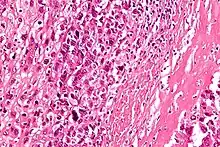

| Intermediate-magnification micrograph of an osteosarcoma (center and right of image) adjacent to non-malignant bone (left-bottom of image): The top-right of the image has poorly differentiated tumor. Osteoid with a high density of malignant cells is seen between the non-malignant bone and poorly differentiated tumor (H&E stain). | |

Microscopically: The characteristic feature of osteosarcoma is presence of osteoid (bone formation) within the tumor. Tumor cells are very pleomorphic (anaplastic), some are giant, numerous atypical mitoses. These cells produce osteoid describing irregular trabeculae (amorphous, eosinophilic/pink) with or without central calcification (hematoxylinophilic/blue, granular)—tumor bone. Tumor cells are included in the osteoid matrix. Depending on the features of the tumor cells present (whether they resemble bone cells, cartilage cells, or fibroblast cells), the tumor can be subclassified. Osteosarcomas may exhibit multinucleated osteoclast-like giant cells.[21]